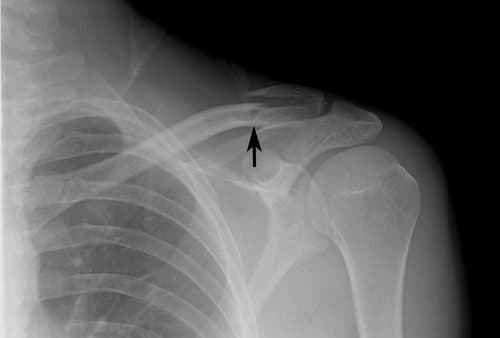

Gãy xương đòn bao lâu chạy xe lại được?

Chào bác sĩ! Em bị gãy 1/3 xương đòn vai phải và mổ phẫu thuật được hai tuần rồi ạ. Vai của em vẫn còn đau nên muốn hỏi gãy xương đòn bao lâu thì hồi phục hoàn toàn và gãy xương đòn bao lâu chạy xe máy lại được ạ? Cần lưu ý gì để […]

Những biến chứng thường gặp của gãy xương đòn

Xương đòn hay còn được gọi là xương quai xanh rất dễ gãy, nó chiếm khoảng 5% các trường hợp gãy xương ở người lớn. Biến chứng gãy xương đòn ảnh hưởng khá nhiều tới sức khỏe và sinh hoạt của người bệnh. Các trường hợp gãy xương đòn xảy ra do bị té ngã […]